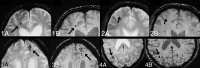

Background and purpose: Cerebral microbleeds are thought to have potentially important clinical implications in dementia and stroke. However, the use of both T2* and SWI MR imaging sequences for microbleed detection has complicated the cross-comparison of study results. We aimed to determine the impact of microbleed sequences on microbleed detection and associated clinical parameters.

Materials and methods: Patients from our memory clinic (n = 246; 53% female; mean age, 62) prospectively underwent 3T MR imaging, with conventional thick-section T2*, thick-section SWI, and conventional thin-section SWI. Microbleeds were assessed separately on thick-section SWI, thin-section SWI, and T2* by 3 raters, with varying neuroradiologic experience. Clinical and radiologic parameters from the dementia investigation were analyzed in association with the number of microbleeds in negative binomial regression analyses.

Results: Prevalence and number of microbleeds were higher on thick-/thin-section SWI (20/21%) compared with T2*(17%). There was no difference in microbleed prevalence/number between thick- and thin-section SWI. Interrater agreement was excellent for all raters and sequences. Univariate comparisons of clinical parameters between patients with and without microbleeds yielded no difference across sequences. In the regression analysis, only minor differences in clinical associations with the number of microbleeds were noted across sequences.